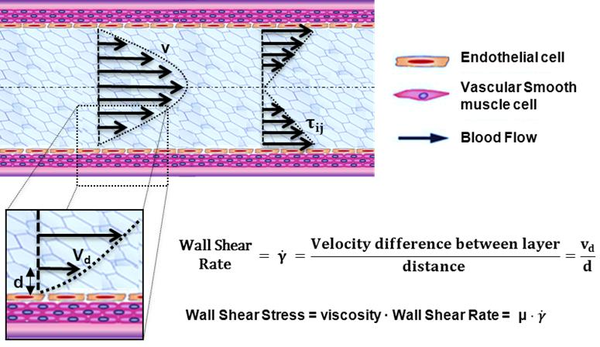

1.4.1 Patient-specific modelling

Patient-specific modeling is the development of computational models of human physiology that are individualized to patient-specific data[63]. Imaging data can be stored in the Digital Imaging and Communication in Medicine (DICOM) format [64]. The DICOM format file contains two parts: the header which stores detailed information about the patient such as name, type of scan, ages, dimension of the image and the voxel, image position, and so forth. The second data set contains information of each scanned image. Segmentation of medical image was required to extract the geometry of the region of interest (or analysis). The segmentation process can include several procedures as threshold, region growing, centerline, among others, followed by 3D anatomical reconstruction to obtain a coarse solid model[65] . During threshold, a range of gray scale values are selected such that the region to be selected is of the best contrast. After the regions of interest are extracted, the voxels are labelling together with an identificator to create the 3D geometry.

In previous work[65] an efficient methodology for pre-processing medical images to generate computational meshes for numerical simulation is explained. A schematic flowchart for creating and validating a 3D patient-specific model is shown in figure 5 of [65]. Aneurysm models (patient-specific geometries) of paper 2 were reconstructed from computer tomography-angiography (CTA) scan using the diagnostic software ITK-SNAP[66] and DIPPO[67].

Both image processing programs employ active contour (deformable models) which move under the action of external forces according to the image intensity and first and second spatial image gradients. A schematic diagram depicting the segmentation of medical image at various locations of the abdominal aneurysm is shown in figure 8. Coronary models of chapter 5 were reconstructed from X-ray coronary angiography (XA). At the moment, X-ray coronary angiography is the standard technique for anatomical assessment and the diagnosis of coronary arteries. The 3D coronary models reconstructed was based on two bi-dimensional images taken from different perspectives. Then the reconstruction of abdominal aneurysm anatomy or coronary into a computational mesh (computer model) is performed based on the segmentation information. To generate the computational mesh GiD pre and ostprocessor[67] and the open source Vascular Modeling Toolkit (VMTK) [26] were used.

When we have a large Reynolds number inertial forces are dominant over viscous forces and viceversa. This naturally leads us to the role of Reynolds number as the key parameter which identifies the transition of the flow to turbulence. Usually, Reynolds number suggests that in most arteries of the cardiovascular system the flow is laminar. The exceptions are the flow in severely stenotic vessels, where the flow regime can be become transitional or turbulent. Turbulence blood flow implies fluctuating pressure acting on the arterial wall, and fluctuating, increased shear stress, which can be provoke post-stenotic dilation or atherogenesis. In this monograph, blood flow has being considering laminar. Figure 9 shows the full process from the medical image to the numerical simulation: aortic abdominal aneurism imaging, geometry modelling, finite elements meshing and mechanical and hemodynamics numerical simulation.